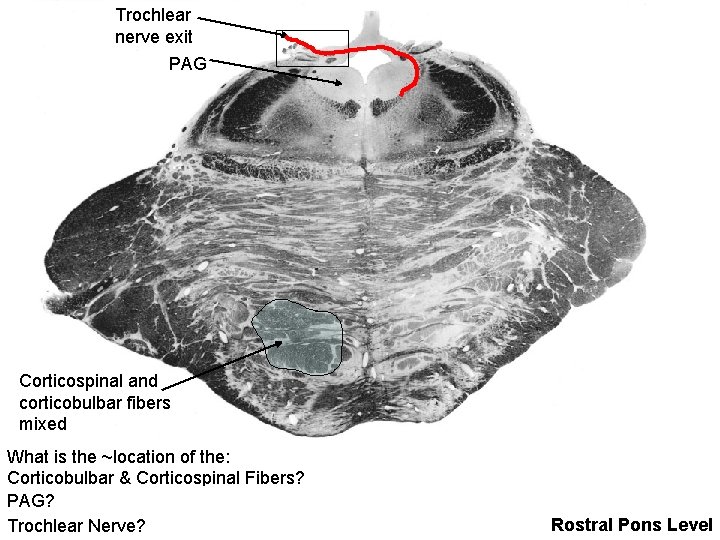

Trochlear nerve exit PAG Corticospinal and corticobulbar fibers mixed What is the ~location of the: Corticobulbar & Corticospinal Fibers? PAG? Trochlear Nerve? Rostral Pons Level